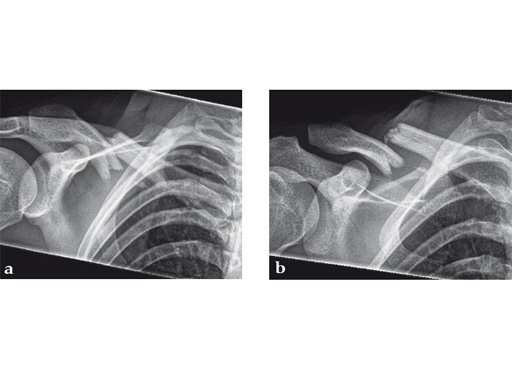

Case 1: a 30-year-old woman sustained a midshaft clavicle fracture. it healed with 2.1 cm shortening over 4 years after nonoperative treatment.

Case provided by Norbert Sdkamp and Martin Jaeger, Freiburg, Germany